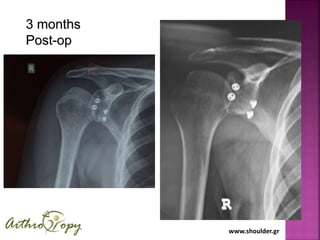

Arthroscopic Bone Block

combined with Remplissage

3 months

Post-op

Our Results

25 cases

Impressive early outcomes